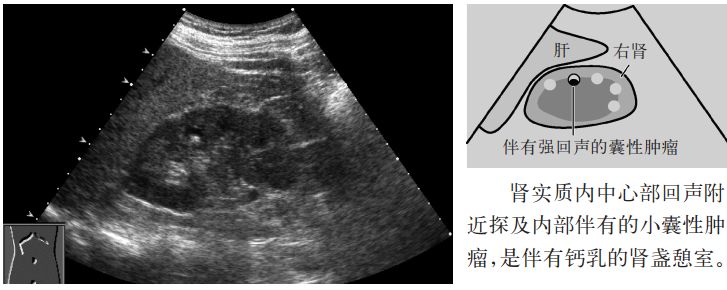

图3 肾盏憩室

(1)中心部回声(集合系统)附近可探及囊性肿瘤,与单纯性囊肿比较其形状不规则及后方回声增强略差。

(2)肾盏憩室可伴有结石或钙乳。